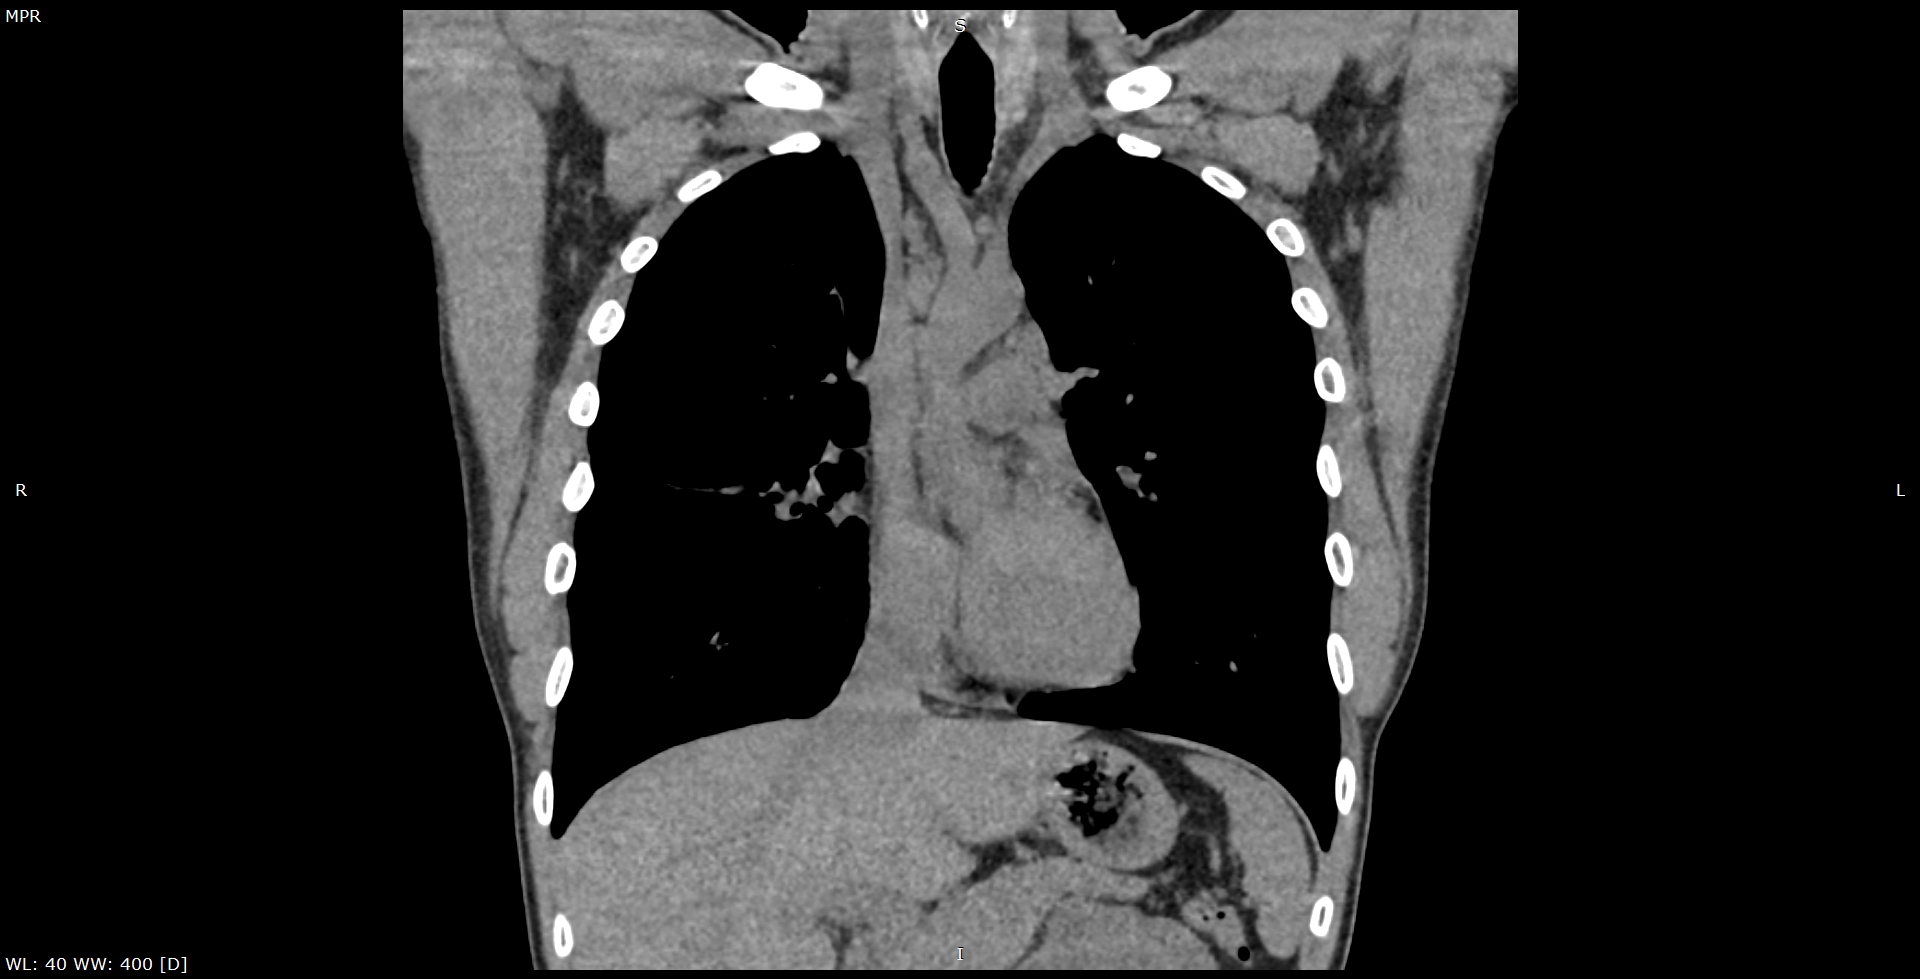

Мультиспиральная КТ лимфатических узлов направлено на изучение структуры лимфоузлов и их взаимоотношения с близлежащими органами и окружающими тканями. Исследование проводится прицельно в той области, где имеются увеличенные болезненные или безболезненные лимфатические узлы.

В клинике «Доступная медицина» исследование проводится на современном компьютерном томографе экспертного класса TOSHIBA AQUILION CXL, производящего большое количество тончайших срезов исследуемой зоны и преобразующего полученные данные в 3D-изображения высокой четкости и контрастности. Аппарат оснащен большим количеством высокочувствительных детекторов, которые улавливают сигналы при сканировании за несколько секунд, что существенно сокращает время исследования и снижает лучевую нагрузку на организм пациента.

При необходимости выявления злокачественной инфильтрации лимфоузлов, исключения их метастатического поражения проводится КТ лимфоузлов с контрастным усилением. Внутривенно введенный контрастный препарат, имеющий в своем составе йодсодержащее вещество, накапливается в измененных тканях и делает их более четкими для визуализации. МСКТ с внутривенным болюсным контрастированием дает возможность диагностировать онкологические процессы на ранней стадии, что имеет решающее значение для эффективного и своевременного лечения.